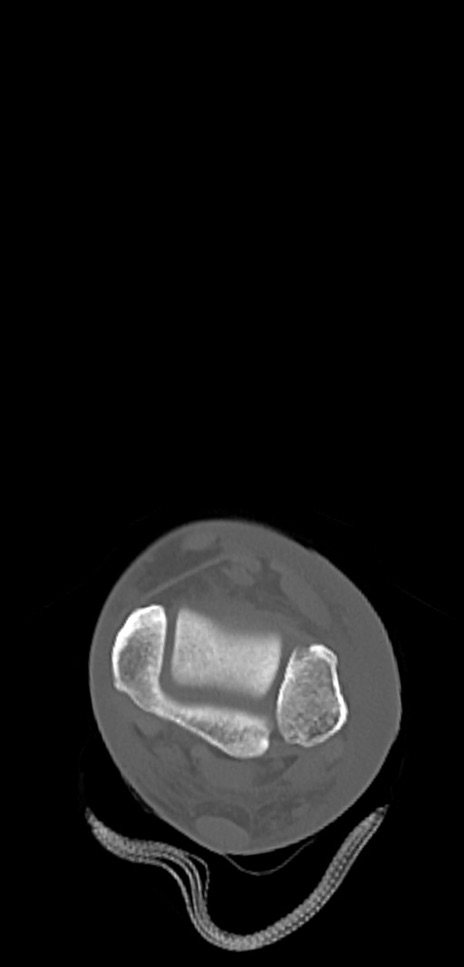

症例37 左足関節CT(横断像)

左足関節CT